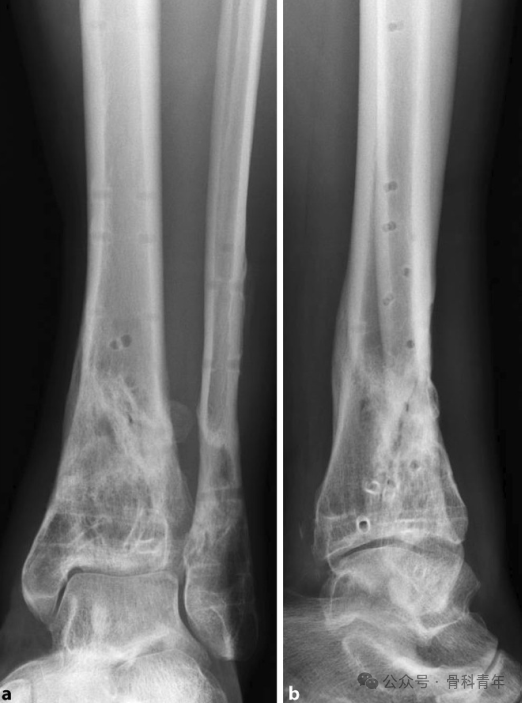

恢复腓骨长度; -

恢复胫骨远端关节面平整; -

胫骨干骺端植骨; -

胫骨内侧钢板固定。